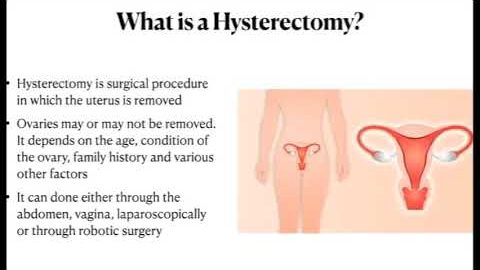

PCOS: Polycystic Ovary Syndrome

Perioperative surgical outcomes of patients undergoing hysterectomy

Arm reduced Robotic Hysterectomy with Transvaginal cuff closure- Analysis

Robotic Hysterectomy for Bigger Uterus

Rationale of Managing Large Uterine Masses- Hysterectomy